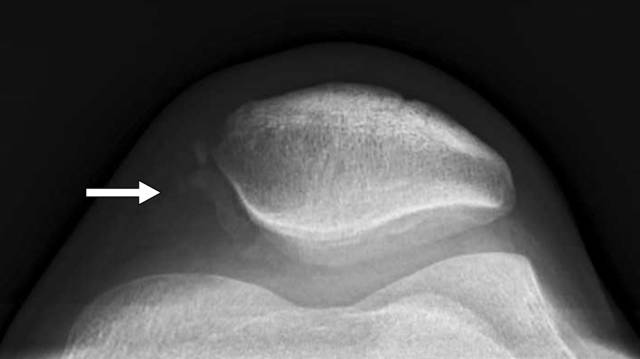

在膝关节处,髌骨的骨折可能不明显,除非获得轴向髌骨视图(图1)。缺乏体重视图可导致跗横关节或跗跖关节(Lisfranc or Chopart joint)损伤的假阴性射线照相结果[5,6]。压力观察可能是必要的,以显示对踝臼或下胫腓分离

图1〜20岁的男性患者出现短暂的外侧髌骨脱位。骨折在侧位和前后位X线照片上不可见。轴位视图显示沿着髌骨的中间边缘的多个撕裂碎片(箭头)。